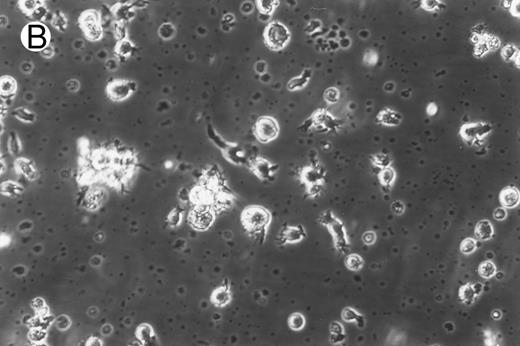

Morphology of freshly isolated and cultured CML cells. PBMNCs from chronic-phase CML patients were isolated and cultured as described in the Materials and Methods. The results depicted are phase-contrast micrographs of freshly isolated cells (A) and after 10 days of culture in the presence of GM-CSF, IL-4, and TNF-α (B).

Generation of dendritic cells in vitro.Freshly isolated PBMNCs of CML patients appeared as dispersed, spherical cells with a smooth surface morphology (Fig 1A). After 3 to 4 days of culture, the cells appeared larger and were associated in nonadherent grape-like clusters with short projections emerging from the surface. Between days 7 and 10, in clusters or dispersed, nonadherent cells with large-cell bodies and long dendritic projections were the predominant population (Fig 1B). In addition, there was a minor but significant population of strongly adherent macrophages. Beginning with an initial population of 10 × 106 cells, 2.4 ± 1.8 × 106 viable cells were recovered on day 2, 3.9 ± 1.6 × 106 cells were recovered on day 8, and 4.6 ± 2.2 × 106 cells were recovered on day 14. On days 0 and 2, less than 1% of these cells exhibited a dendritic morphology. The numbers of cells with a dendritic morphology increased to 24% ± 6% after 8 days and 53% ± 14% on day 14 of culture (n = 9). The viability and dendritic morphology of these cells could be maintained for up to 29 days by transferring the nonadherent cells into fresh medium containing GM-CSF, IL-4, and TNF-α every 3 to 4 days. No significant increase in cell numbers was noted after days 14 to 18.